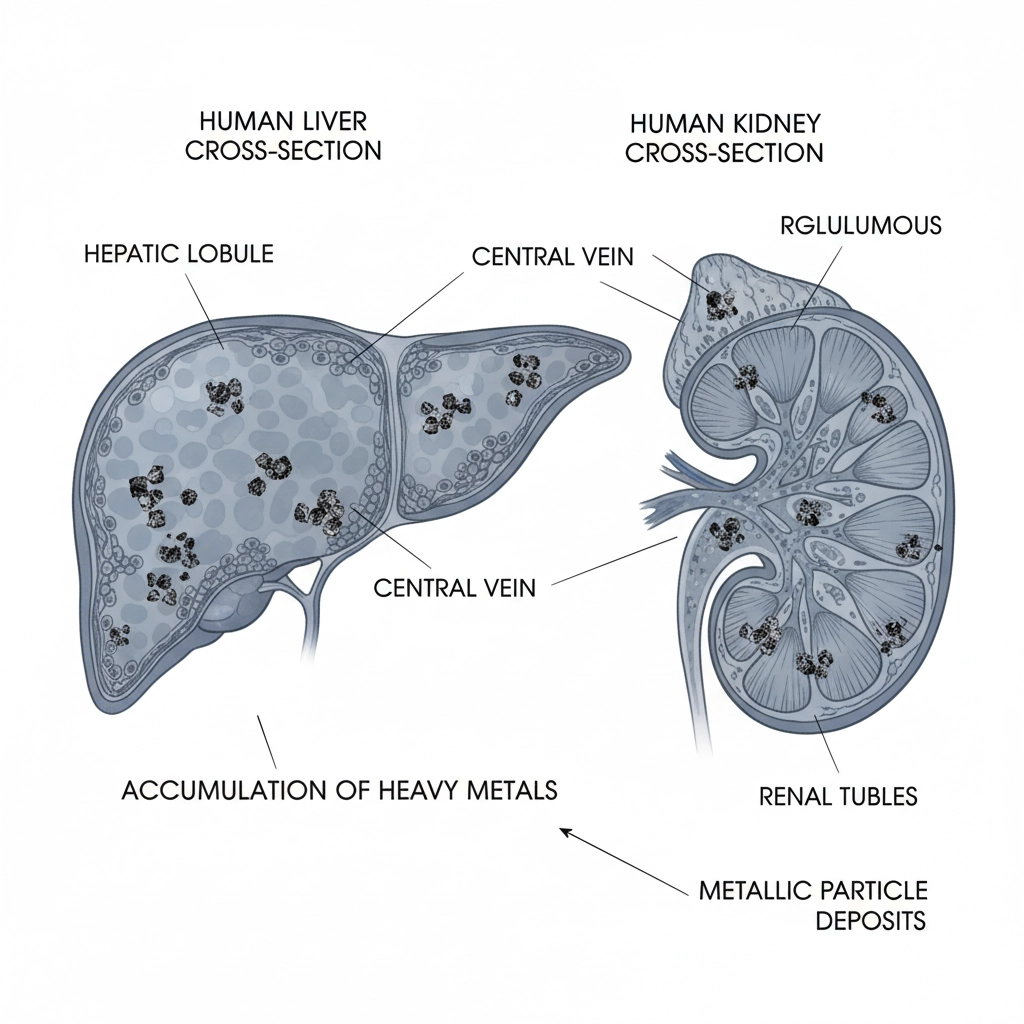

✅ ELIMINATE TOXINS that slow recovery

- Ice: Risk of frostbite, nerve damage, and tissue necrosis

- Clayer: CERTIFIED 100% NATURAL, NON-TOXIC, DOPING-FREE

- No risk of cold burns or tissue damage

- 100% NATURAL INGREDIENTS